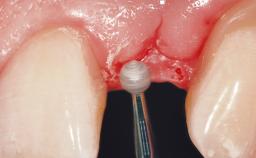

Immediate Placement of an Implant in a Maxillary Left Central Incisor Site

A 33-year-old female patient presented with an upper left central incisor that required extraction after a failed endodontic therapy. The tooth had been traumatized when the patient was a teenager and had undergone several endodontic treatments, including two apicectomy procedures. The patient was in good health and did not smoke. Clinical examination showed that the patient had a high lip line. In full smile, the gingival margins of the upper teeth were visible to the first molars. The gingival margins of central incisors 11 and 21 were only just showing. Examination of tooth 21 confirmed that the tooth was mobile and had hypererupted by 1 mm.

| Soft Tissue Grafting | Simultaneous |

| Soft Tissue Contour and Volume | Slightly compromised |